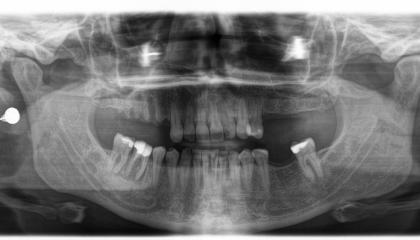

Zirconia bridge on Southern DC Implants

Tooth Replacement

Zirconia Implants

Single Dental Implant